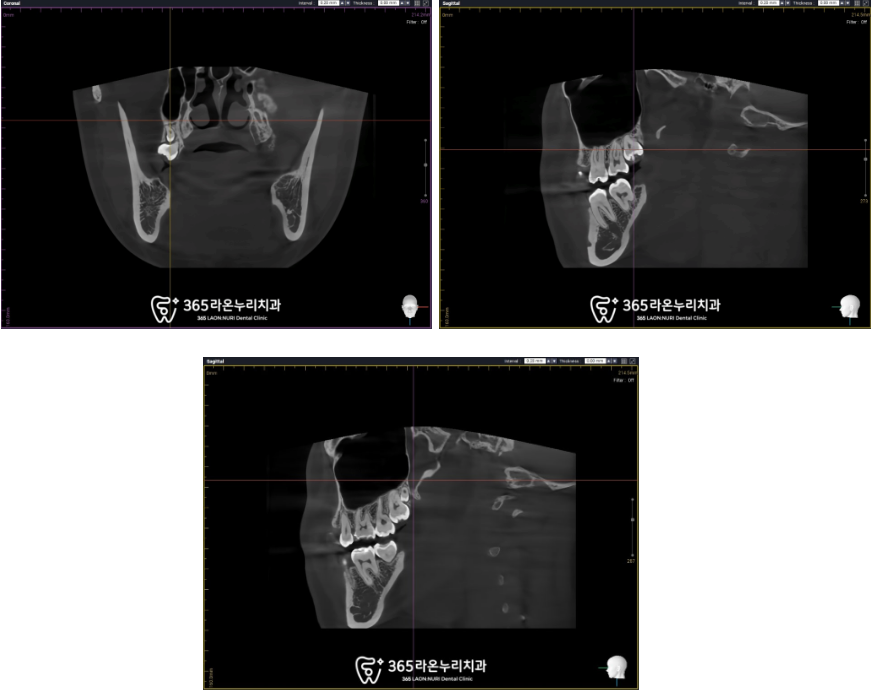

발치 전 위치 관계를 확인하기

위해 CT도 촬영을 하고,

안전하게 발치 과정을 준비하게 됩니다.

25. 06. 22

여러 각도에서 CT를 확인해보고

안전하게 발치 과정을 차근차근 확인하게 됩니다.